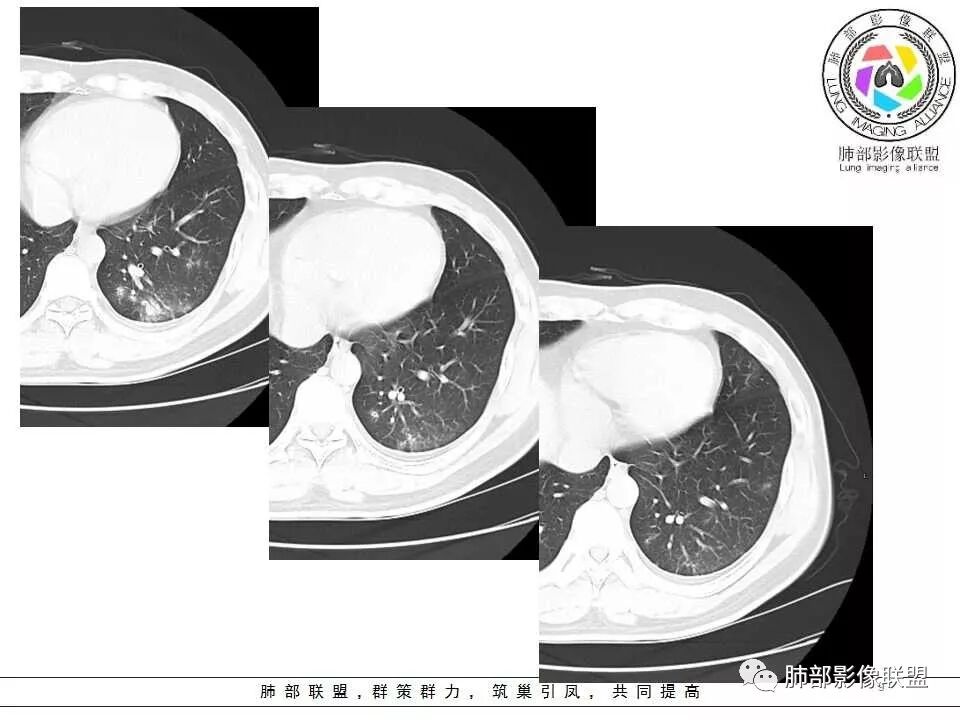

影像资料

左肺下叶肿块,密度不均,其内有低密度坏死,周围有晕,支气管进入阻塞,长轴平行胸膜,周围可见形态密度一致小病灶,考虑隐球菌。鉴别淋巴瘤。

青年男性,急性起病,左肺下叶近胸膜可见实变及结节影,宽基底与胸膜相连,胸膜下脂肪间隙可见,支气管部分中断,未见树芽,良性病变,考虑隐球菌可能,鉴别结核。

左肺下叶实变,长轴与胸膜平行,边缘平直、膨隆,周围有边缘模糊晕,近端支气管进入病灶,內有低密度坏死,邻近胸膜弥漫性增厚,胸膜外间隙增宽;病灶周围肺野有多个斑片,部分内有扩张小支气管。青年男性,病史10天,考虑炎性,1、隐球菌,2、TB。

青年男性,咳嗽、左侧胸痛10余天。血常规(一)。左下肺胸膜下见一肿块影,糊墙,长轴与胸膜平行(碰到胸膜往两侧走),近端支气管进入后堵塞,内有小片状低密度区,边缘见模糊的GGO。肿块周围见类似密度的小结节。综上考虑良性病变,隐球菌可能性大。

青年男性,左肺下叶实变影,长轴与胸膜平行,支气管进入后堵塞,边缘晕征,略膨隆,内有低密度影。结合病史,咳嗽,咳痰。考虑:炎性肉芽肿,隐球菌感染。建议检查隐球菌抗原、增强或穿刺活检。鉴别,淋巴瘤,肺链。

青年男性,无发热,呼吸痛,体重下降。左肺下叶实变,宽基底,气管进入后截断,周边有模糊的晕,晕中带刺儿,内见多发小坏死,收缩为主,稍有膨隆,糊墙,多发病灶,支持隐球。

左肺下叶胸膜下肿块,密度不均,内见低密度坏死区,病灶边缘有膨隆,也有收缩,周围有晕,支气管进入近端阻塞,远端支气管走行通畅,病灶长轴平行胸膜,胸膜糊墙,周围可见多发类似结节,形态单一,考虑感染性病变,隐球菌?

青年男性,左肺下叶实变影,长轴与胸膜平行,支气管进入后闭塞略扩张,边缘晕征,略膨隆,内有低密度影,糊墙,周围小结节状小片状影类似,考虑炎性病变,隐球菌可能,不除外一般炎症并小脓肿形成,建议结合临床和隐球菌抗原检查。

青年男性,咳嗽,胸痛10天,白细胞不高,中性粒细胞不高,1月前有发热史,1年内体重下降10公斤,胸部CT所见左肺下叶跨背段及后基底段不规则形团块影,宽基底与胸膜相连,胸膜下脂肪间隙清楚(糊墙),长轴平行胸膜,内有坏死,边缘毛糙,周围见晕征,病灶旁有斑点状及小结节状影,病灶由外向内包绕支气管,考虑:炎性肉芽肿,隐球菌可能,结核待排,查隐球菌荚膜实验,必要时痰检及结核相关检查。

男性,29岁。咳嗽伴左侧胸痛10余天,吸气时胸痛加重,无发热/咳血盗汗。左肺下叶背段斑片样阴影,部分边缘欠清,周围可见小片状偏高密度影,近胸膜面分布。支气管进入病灶内,感觉走形较柔软,主体病灶长轴与支气管垂直,壁层胸膜下脂肪间隙可见,病灶内似可见更低密度影。结合临床,考虑炎性病变,隐球可能性大,结核抗体弱阳性,还是要待排的。

左肺下叶胸膜下片状高密度影,密度均匀,近端支气管进入后阻断,形态欠规则,边缘GGO模糊,病灶长轴与胸膜平行,与相邻胸膜呈糊墙改变,相应胸膜增厚,考虑炎性病变,隐球菌可能性大。

左肺下叶胸膜下多发病灶,支气管进入有堵塞,长轴平行胸膜,糊墙,考虑炎性病变可能性大 ,隐球菌首先考虑。待排粘液腺癌。

青年男性,左肺下叶团片影,支气管进入有堵塞,病灶边缘有晕,周围散在相似小病灶,病灶胸膜平行,考虑炎性病变,隐球菌?

左肺下叶胸膜下肿块,支气管进入有堵塞,长轴平行胸膜,内部有坏死,考虑炎性病变 ,考虑隐球菌。

青年男性,咳嗽咳痰胸痛,有发热史,体重下降,结核抗体弱阳性。胸部CT所见左肺下叶跨背段及后基底段不规则形团块影,边界相对清楚,内部似见坏死,病灶沿胸膜下平行于胸膜横向发展,邻近胸膜增厚,周围见边界不清磨玻璃密度影。左肺下叶背段及后基底段近肋膈角区见多发较小形态及密度相似结节,部分结节周围见条索影。综合考虑炎性病变,隐球菌感染可能性大,建议查隐球菌荚膜实验,询问有无鸽子接触史等。

青年男性,咳嗽无发热,结核抗体阳性,体重下降明显,CT影像示左肺下叶团片状高密度灶,形态欠规整,周围见斑点片状卫星灶,病灶中心部分坏死,宽基底与胸膜相连,支气管穿行,管壁光滑,远端似见闭塞,余肺未见明显异常,倾向考虑感染性病变。